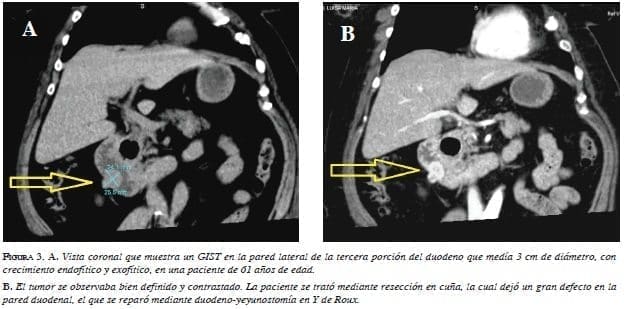

El estudio radiológico con mayor disponibilidad en la actualidad para identificar y diagnosticar GIST, es la tomografía computadorizada (TC). Prácticamente todos los GIST duodenales son detectados con TC 17,18,29. Los GIST son tumores hipervasculares que en imágenes muestran un intenso contraste en la fase arterial 15. La mayoría muestra un contraste homogéneo y aparecen como masas endofíticas o exofíticas bien definidas 29-33. Los tumores pequeños se muestran como masas homogéneas bien delineadas ovaladas o redondas contrastadas moderadamente 29,31,33-36 (figura 1). Los GIST grandes pueden presentar ulceración de la mucosa, se observan bien contrastados, bien delimitados, lobulados y heterogéneos, pueden presentar necrosis central, cavitación, líquido y crecimiento endoluminal y extraluminal 7,17,29,30, 31,33,37 (figuras 2 y 3).

Los criterios tomográficos para la descripción y el registro de GIST fueron establecidos por Burkill, et al. 31,32 (tabla 5). Los GIST evidentemente malignos presentan metástasis hepáticas o invasión local de los tejidos y órganos circundantes 29-37.